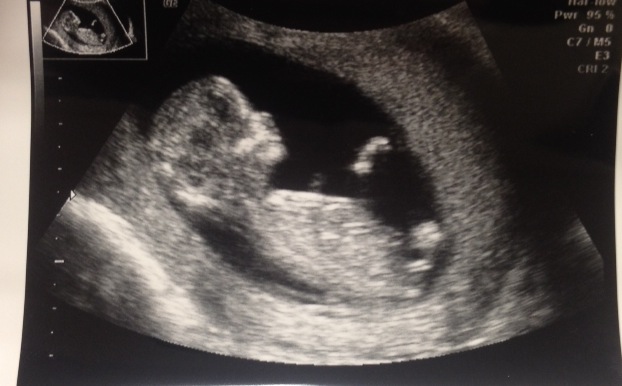

This is at 12 weeks and 5 days. I've heard it looks boyish, but I can't tell! Any insight would be great!Attachment 20782

I agree, does look like a little boy, congrats!

Looks boyish.

Looks boy skull too